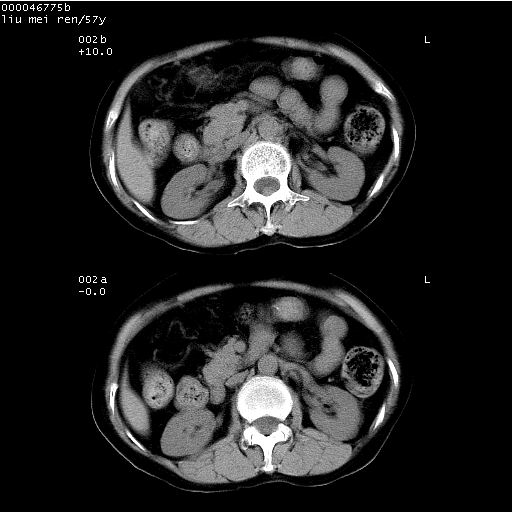

患者 女,57岁。因车祸受伤,其家属要求行“全身ct检查”。平素健康。

胸部ct轴位平扫(层厚10mm,螺距1.5,重建间隔10mm),图像如下: